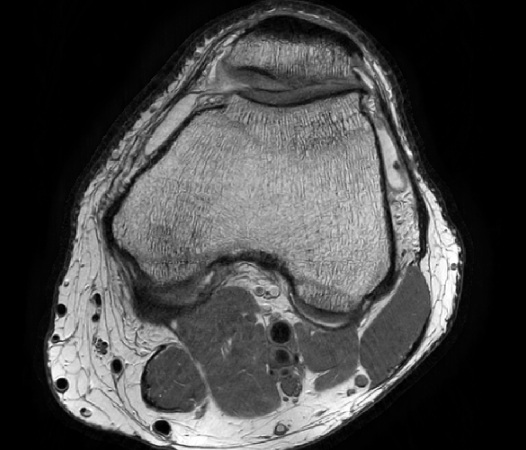

Compressed SENSE is the latest Philips MRI acceleration method, based on our industry leading dStream architecture. Compressed SENSE further expands the performance of dS SENSE, making MRI scans up to an additional 50% faster*, with virtually identical image quality. Alternatively, Compressed SENSE can increase the image resolution up to 40% within the same scan time. Compressed SENSE can be applied to all anatomies and works for both 3D as well as for 2D MRI acquisitions, making it a powerful asset for almost all clinical MRI exams.